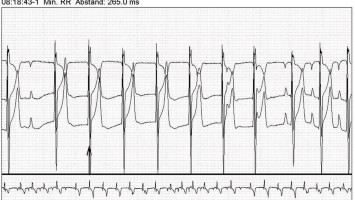

Kardiogener Schock durch Tachykardiomyopathie

Bei der Aufnahme weist der Patient einen stark reduzierten Allgemeinzustand auf. Seine Blutdruckwerte sind hypoton (107/74 mmHg) und er zeigt eine Tachykardie (125 Schläge pro Minute) mit unregelmäßigen Herzaktionen bei Vorhofflimmern. Die …

Digitales Blutdruckmessgerät/© Kotchakorn / Stock.adobe.com (Symbolbild mit Fotomodell), Injektionsnadeln für Regionalanästhesie/© zlikovec / Getty Images / iStock, Reanimation/© Rea / stock.adobe.com, Langzeit-EKG mit junktionalem Ersatzrhythmus/© O. Schäfer, Fokussierter Herzultraschall (FoCUS)/© Dieter von Ow / all rights reserved Springer Medizin Verlag GmbH, Pulsoximeter wird an Finger angeschlossen/© Yakobchuk Olena / stock.adobe.com, Rhabdomyom im Kindesalter /© Höck M et al. doi.org/10.1007/s00112-025-02259-w unter CC-BY 4.0, Eine Pinzette wird vom Tisch genommen während einer OP/© JazzIRT / Getty Images / iStock (Symbolbild mit Fotomodellen), Venöse CT-Angiografie: Sinusthrombose/© Wohlfahrt L. et al. / all rights reserved Springer Medizin Verlag GmbH, Übergabesituation im Herzkatheterlabor/© Ernst M et al. / all rights reserved Springer Medizin Verlag GmbH (Symbolbild mit Fotomodellen), Frau misst Blutdruck/© Microgen / stock.adobe.com (Symbolbild mit Fotomodell), Transösophageale Echokardiographie (fTEE), 4‑Kammer-Blick/© Michels M et al. / all rights reserved Springer Medizin Verlag GmbH, Screening auf Präeklampsie/© Musik T et al. / all rights reserved Springer Medizin Verlag GmbH, Arzt nimmt Schwangeren Blut ab/© Andrey Popov / stock.adobe.com (Symbolbild mit Fotomodellen), Patient im Gespräch mit Ärztin/© sebra / stock.adobe.com (Symbolbild mit Fotomodellen), Mann hält Tablette und ein Glas Wasser in den Händen/© somenski / Fotolia (Symbolbild mit Fotomodell), Herpes Zoster am Rücken/© Mumemories / Getty Images / iStock (Symbolbild mit Fotomodell), EKG befunden mit System - EKG Essential/© Springer Medizin Verlag GmbH